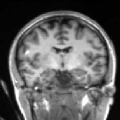

To compare the proposed approach to the mSENSE333SENSE reconstruction implemented by the Siemens scanner, software ICE, VB 17. one, Fig. 1 illustrates coronal anatomical slices reconstructed with both algorithms while turning off the temporal regularization in 4D-UWR-SENSE, so resulting in the so-called 3D-UWR-SENSE approach. Red circles clearly show reconstruction artifacts and noise in the mSENSE reconstruction, which have been removed using our 3D-UWR-SENSE approach. Comparison may also be made through reconstructed slices for and , as well as with the conventional acquisition (). This figure shows that increasing generates more noise and artifacts in mSENSE results whereas the impact on our results is attenuated. Artifacts are smoothed by using the continuity of spatial information across contiguous slices in the wavelet space. Depending on the used wavelet basis and the number of vanishing moments, more or less (4 or 8 for instance) adjacent slices are involved in the reconstruction of a given slice. For instance, using Symmlet filters of length 8 (4 vanishing moments) as in the conducted experiments here, 8 adjacent slices are involved in reconstructing a given slice. However, it is worth noticing that the introduced smoothing is anisotropic, in contrast to standard Gaussian smoothing that could be applied to anatomical data. Fig. 1 also compares 3D-UWR-SENSE and mSENSE reconstructed slices when applying additional spatial smoothing to the later with a mm3 Gaussian kernel. Comparisons clearly show that, even at such low spatial smoothing level, mSENSE images suffer from a significant blur. Moreover, the artifact present at for mSENSE (left red circle) is spread out but not fully removed by applying isotropic spatial smoothing.

Even for slice-selective acquisition schemes where the signal is supposed to be independent between adjacent slices, the proposed algorithm still allows us to exploit information continuity across slices which results from the imaged anatomy. Moreover, the smoothing level strongly depends on the regularization parameters that are used to set the thresholding level of wavelet coefficients. Images reconstructed using our algorithm present higher smoothing level than mSENSE without altering key information in the images. When carefully analysing the image background, one can notice the presence of motion-like artifacts that only affect the background and do not alter the brain mask. Such artifacts are nothing but boundary effects that are due to the use of wavelet transforms.

In order to evaluate the impact of such smoothing, classification tests have been conducted based on images reconstructed with both methods. Gray and white matter classification results using the Morphologist 2012 pipeline of -MRI toolbox of Brainvisa software444http://brainvisa.info at and are compared to those obtained without acceleration (i.e. at ), considered as the ground truth. Displayed results in Fig. 2 show that classification errors occur due to reconstruction artifacts for mSENSE, especially at . Results show that the gray matter is better classified using our 3D-UWR-SENSE algorithm especially next to the artifact into the red circle (Fig. 2 []), which lies at the frontier between the white and gray matters. Moreover, reconstruction noise with mSENSE in the centre of the white matter (left red circle in Fig 2 []) also causes miss-classification errors far from the gray/while matter frontier. However, at and classification performance is rather similar for both methods, which confirms the ability of the proposed method to attenuate reconstruction artifacts while keeping classification results unbiased.